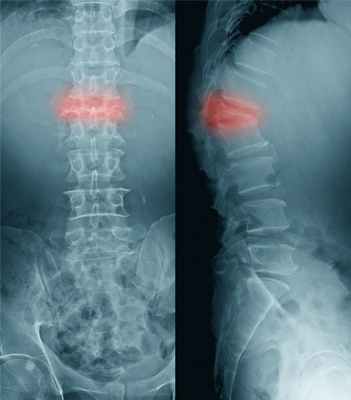

В некоторых случаях переломы могут происходить незаметно для человека – например, компрессионные переломы позвонков, возникающие под воздействием тяжести собственного тела, когда позвонки, пораженные остеопорозом, не справляются с нагрузкой и «сплющиваются».

Компрессионный перелом позвоночника

Заподозрить перелом позвонков при остеопорозе можно, если:

- острая боль, иррадиирущая по типу корешковой боли в грудную клетку, брюшную полость или бедро, резко ограничивающая движения, усиливающаяся при минимальных движениях;

- боль в спине появилась после падения с высоты собственного роста или после подъема тяжелых предметов, которая не проходит после приема нестероидных противовоспалительных препаратов;

- уменьшился рост;

- чувство усталости в спине после вынужденного пребывания в одном положении или ходьбы;

- «ощущение тяжести» между лопатками.

Физикальное обследование включает:

- измерение роста пациента (уменьшение роста на 2 см и более за 1-3 года или на 4 см и более по сравнению с возрастом в 25 лет отражает снижение высоты позвонков при компрессии);

- измерение расстояния между затылком и стеной при измерении роста (если это расстояние составляет более 5см, то можно говорить о грудном кифозе);

- измерение расстояния между нижними ребрами и крылом подвздошной кости (если это расстояние составляет ширину 2-х пальцев и менее, то можно говорить об укорочении позвоночного столба из-за компрессий позвонков).